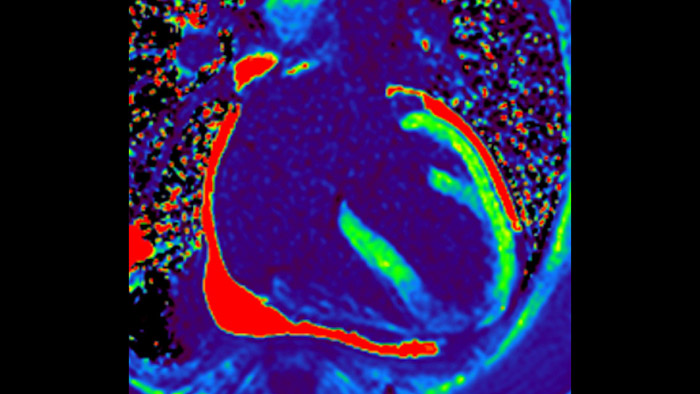

IntelliSpace Portal MR CaaS5,6 Strain7 supporta nella diagnosi e nel monitoraggio dei pazienti fornendo parametri globali di strain, quali strain longitudinale globale (GLS), strain circonferenziale globale (GCS) e strain radiale globale (GRS), utilizzando immagini RM in asse corto e lungo e descrivendo inoltre la deformazione del miocardio, come il suo accorciamento, ispessimento e allungamento durante il ciclo cardiaco.

La diagnostica tradizionale non offre la visibilità necessaria per vedere gli effetti di un trattamento cardiaco o individuare disfunzioni prima che si verifichino i sintomi. Combinando la sequenza di acquisizione MRI Fast-SENC di Philips con lo strumento di analisi MyoStrain di Myocardial Solutions, i lievi cambiamenti precoci nella funzione cardiaca possono essere misurati direttamente.